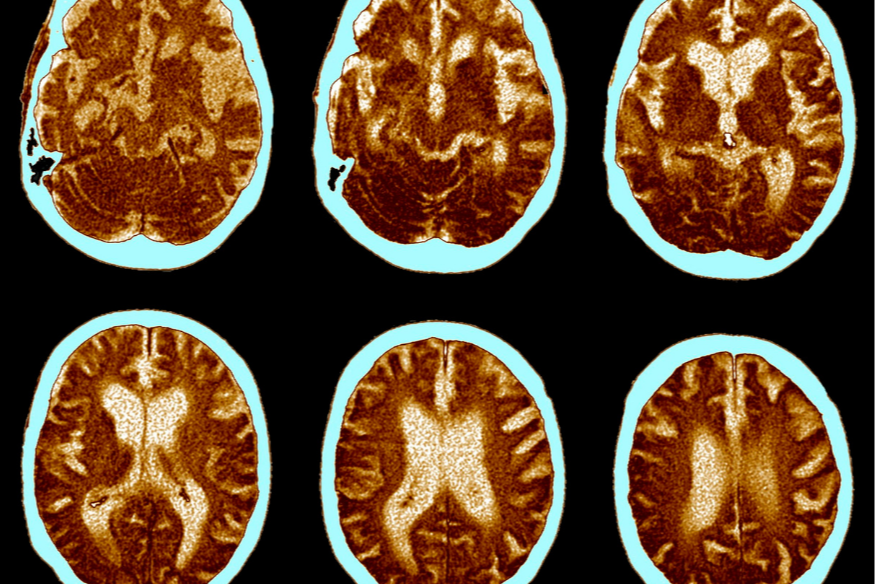

Le Nouvion : un hôpital de jour pour les personnes atteintes de maladies neurodégénératives.

Depuis ce mois de septembre, l’hôpital de la commune a ouvert cet hôpital de jour pour améliorer le diagnostic et la prise en chargé grâce à une journée complète d’évaluation par une équipe pluridisciplinaire. Neurologues, orthophonistes, kinés, ergothérapeutes. Le service peut accueillir 8 patients par jour, il est ouvert chaque mardi.